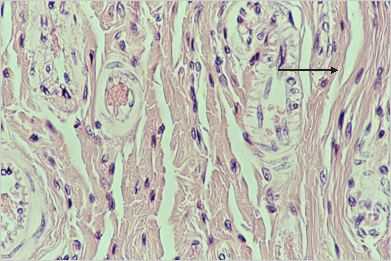

Décollement (diapo 3)

art3p.jpg (17762 octets)